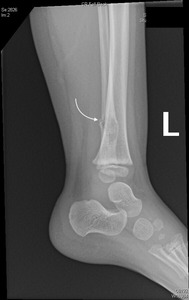

Imaging (CT scan) revealed a pathologic left fibular fracture [Figure 1].

An approximately 0.9 x 1 x 1.3 cm, ill-defined heterogeneous lytic lesion in the distal diaphysis of the left fibula was observed that caused the fracture [Figure 2].